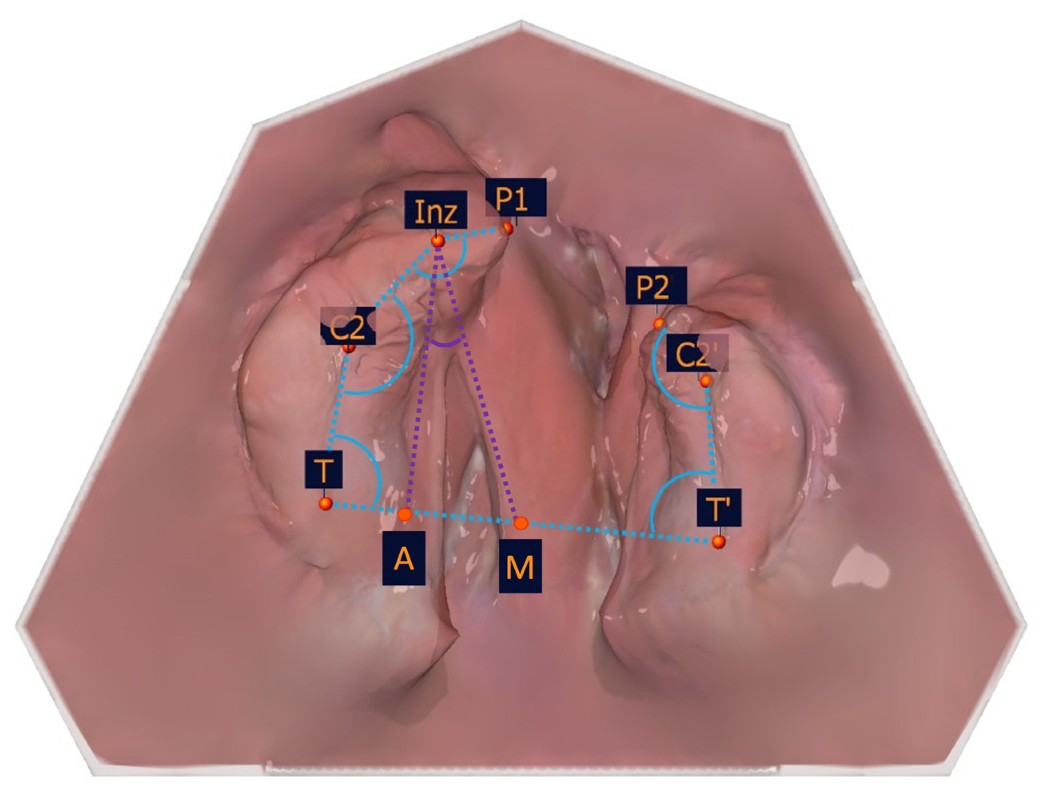

The following constructed measuring points are based on the measurement points listed in Table 1 and are shown in Table 3 and Figure 6. These and the measurement points form the basis for the subsequent distance and angle measurements.

Figure 6. Illustration of the constructed measuring points. The constructed measuring points and their description are presented in Table 3.